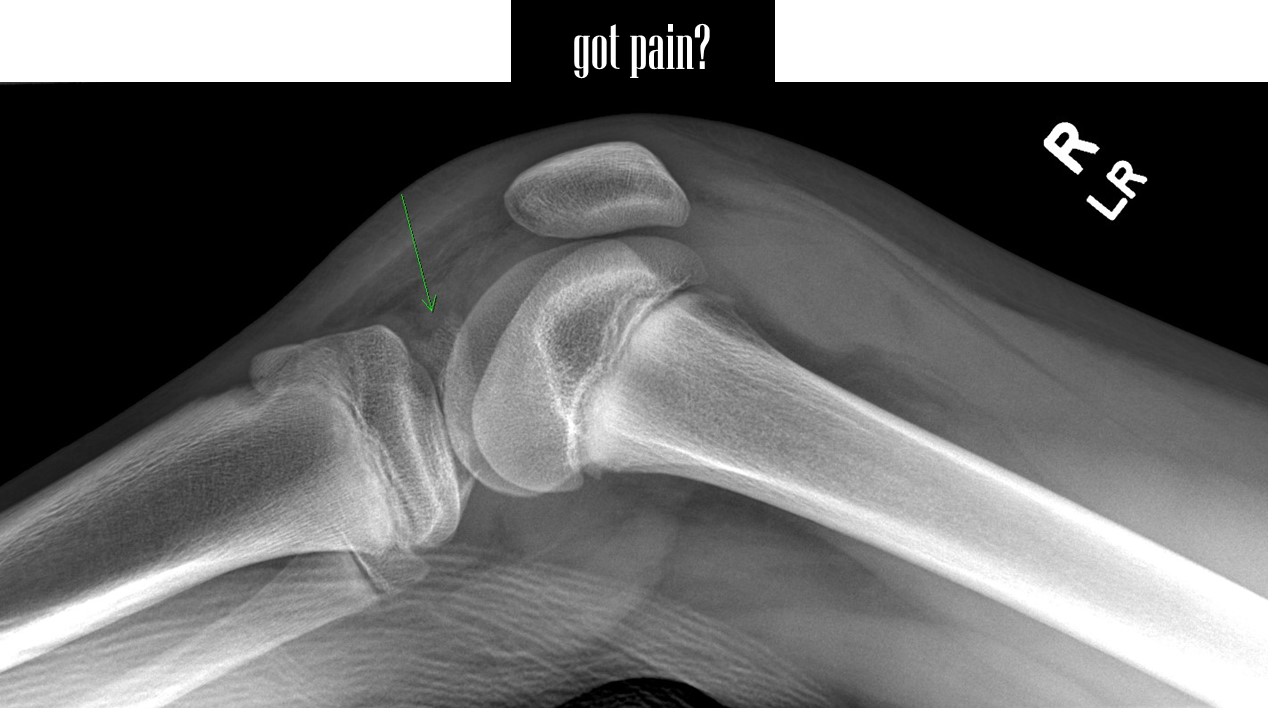

A tibial spine avulsion fracture — an injury requiring surgery, and significant pain management.

The new academic year has begun in North America, and with it a new set of sporting seasons and a surge in sports’ injuries in our clinics. Youth and school soccer and football provide many of the injured patients I manage. For instance, a few days ago, on a Friday, I saw a 12-year-old boy who described a twisting injury to his knee, with immediate disability and an effusion. I saw him in my clinic the day after his injury and discovered he had sustained a tibial spine avulsion fracture.

These injuries typically occur in skeletally immature patients aged 8 to 14 who sustain twisting or valgus moments to a hyperextended knee. Though relatively uncommon, a tibial spine avulsion fracture is seen rather often in a specialty center like mine that focuses on the care of the pediatric and adolescent athlete.